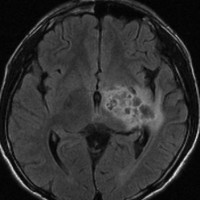

ICE化学療法投与開始から数日で小さくなります

この例は古いので第3脳室開窓術 ETV をしていません。左はICE化学療法前。中央は9日後。右は25日後です。閉塞性水頭症があっても1週間くらいで中脳水道が通って水頭症は改善します。ジャーミノーマであれば,ICE化学療法1コースでかなり縮小するはずです。このような顕著な効果がない時には,逆にジャーミノーマ以外の胚細胞腫瘍が混在していると考えた方がいいでしょう。多くは奇形腫の混在です。